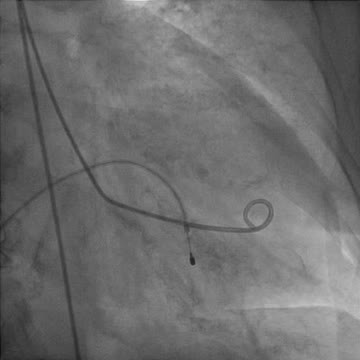

The echocardiography performed at this time confirmed the resolution of LV systolic function and wall-motion abnormalities. However, the complete AV block persisted and, consequently, a dual-chamber pacemaker was implanted (Figure 5). Pacemaker check at one year identified persistent complete heart block but the patient was asymptomatic.